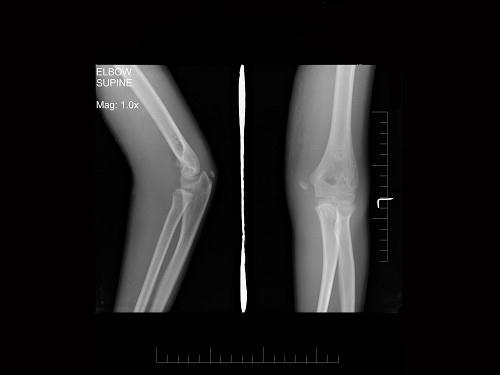

问题 男,11岁,左肘外伤,根据所示图像,最可能的诊断是?(?)

选项 A.左肱骨内上髁骨骺Ⅰ度分离 B.左肱骨内上髁骨骺Ⅱ度分离 C.左肱骨内上髁骨骺Ⅲ度分离 D.左肱骨内上髁骨骺Ⅳ度分离 E.左肱骨内上髁骨骺Ⅴ度分离

答案 A